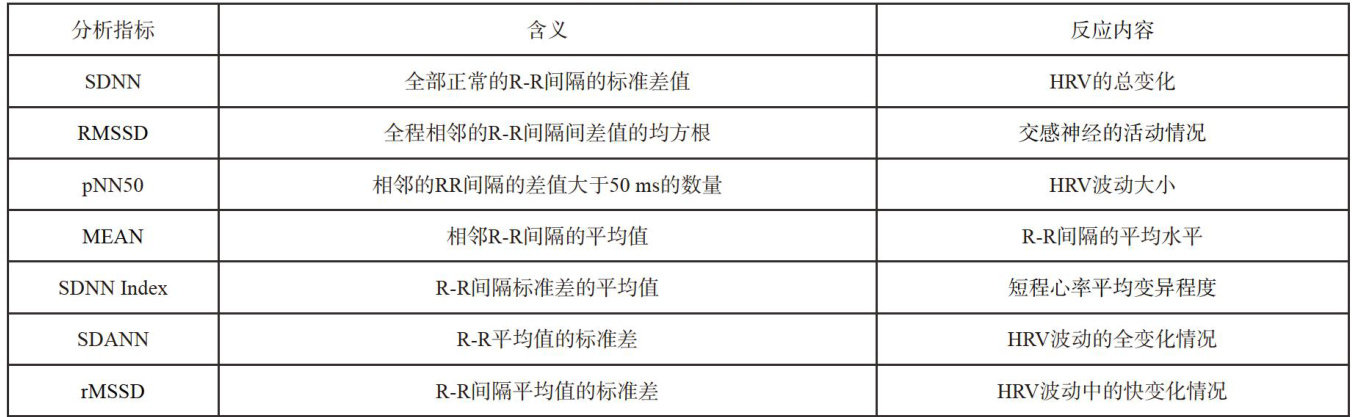

疾病防治 | 应用心率变异性(HRV) 监测马匹赛前状态意义浅析

疾病防治 | 应用心率变异性(HRV) 监测马匹赛前状态意义浅析